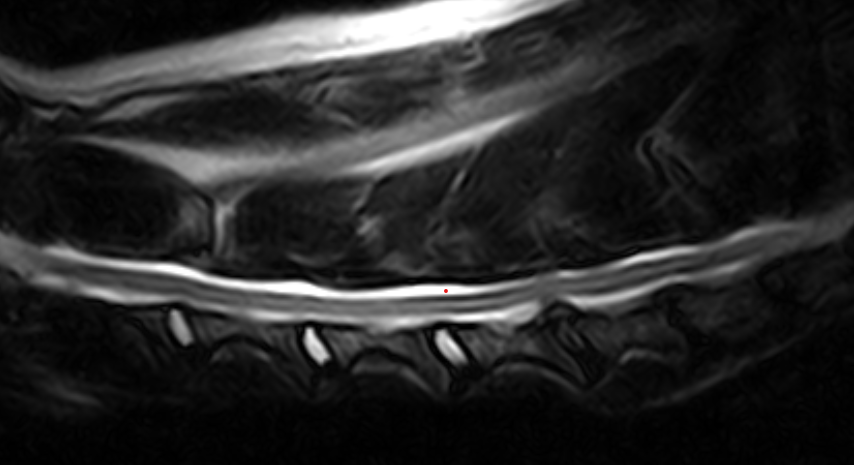

Imágenes de Calidad Premium

IMÁGENES CLÍNICAS

En la sección de imágenes clínicas, destacamos la precisión y claridad de nuestros estudios, respaldados por un equipo de radiólogos especializados en medicina veterinaria. Nos enorgullece ser un aliado confiable para veterinarios y clínicas, brindando un servicio rápido y eficiente para ayudar en la toma de decisiones clínicas fundamentadas.